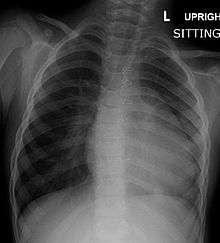

Before more sophisticated techniques became available, chest x-ray was the definitive method of diagnosis. The abnormal "coeur-en-sabot" (boot-like) appearance of a heart with tetralogy of Fallot is classically visible via chest x-ray, although most infants with tetralogy may not show this finding.[21] Absence of interstitial lung markings secondary to pulmonary oligaemia are another classic finding in tetralogy,[22] as is the pulmonary bay sign.